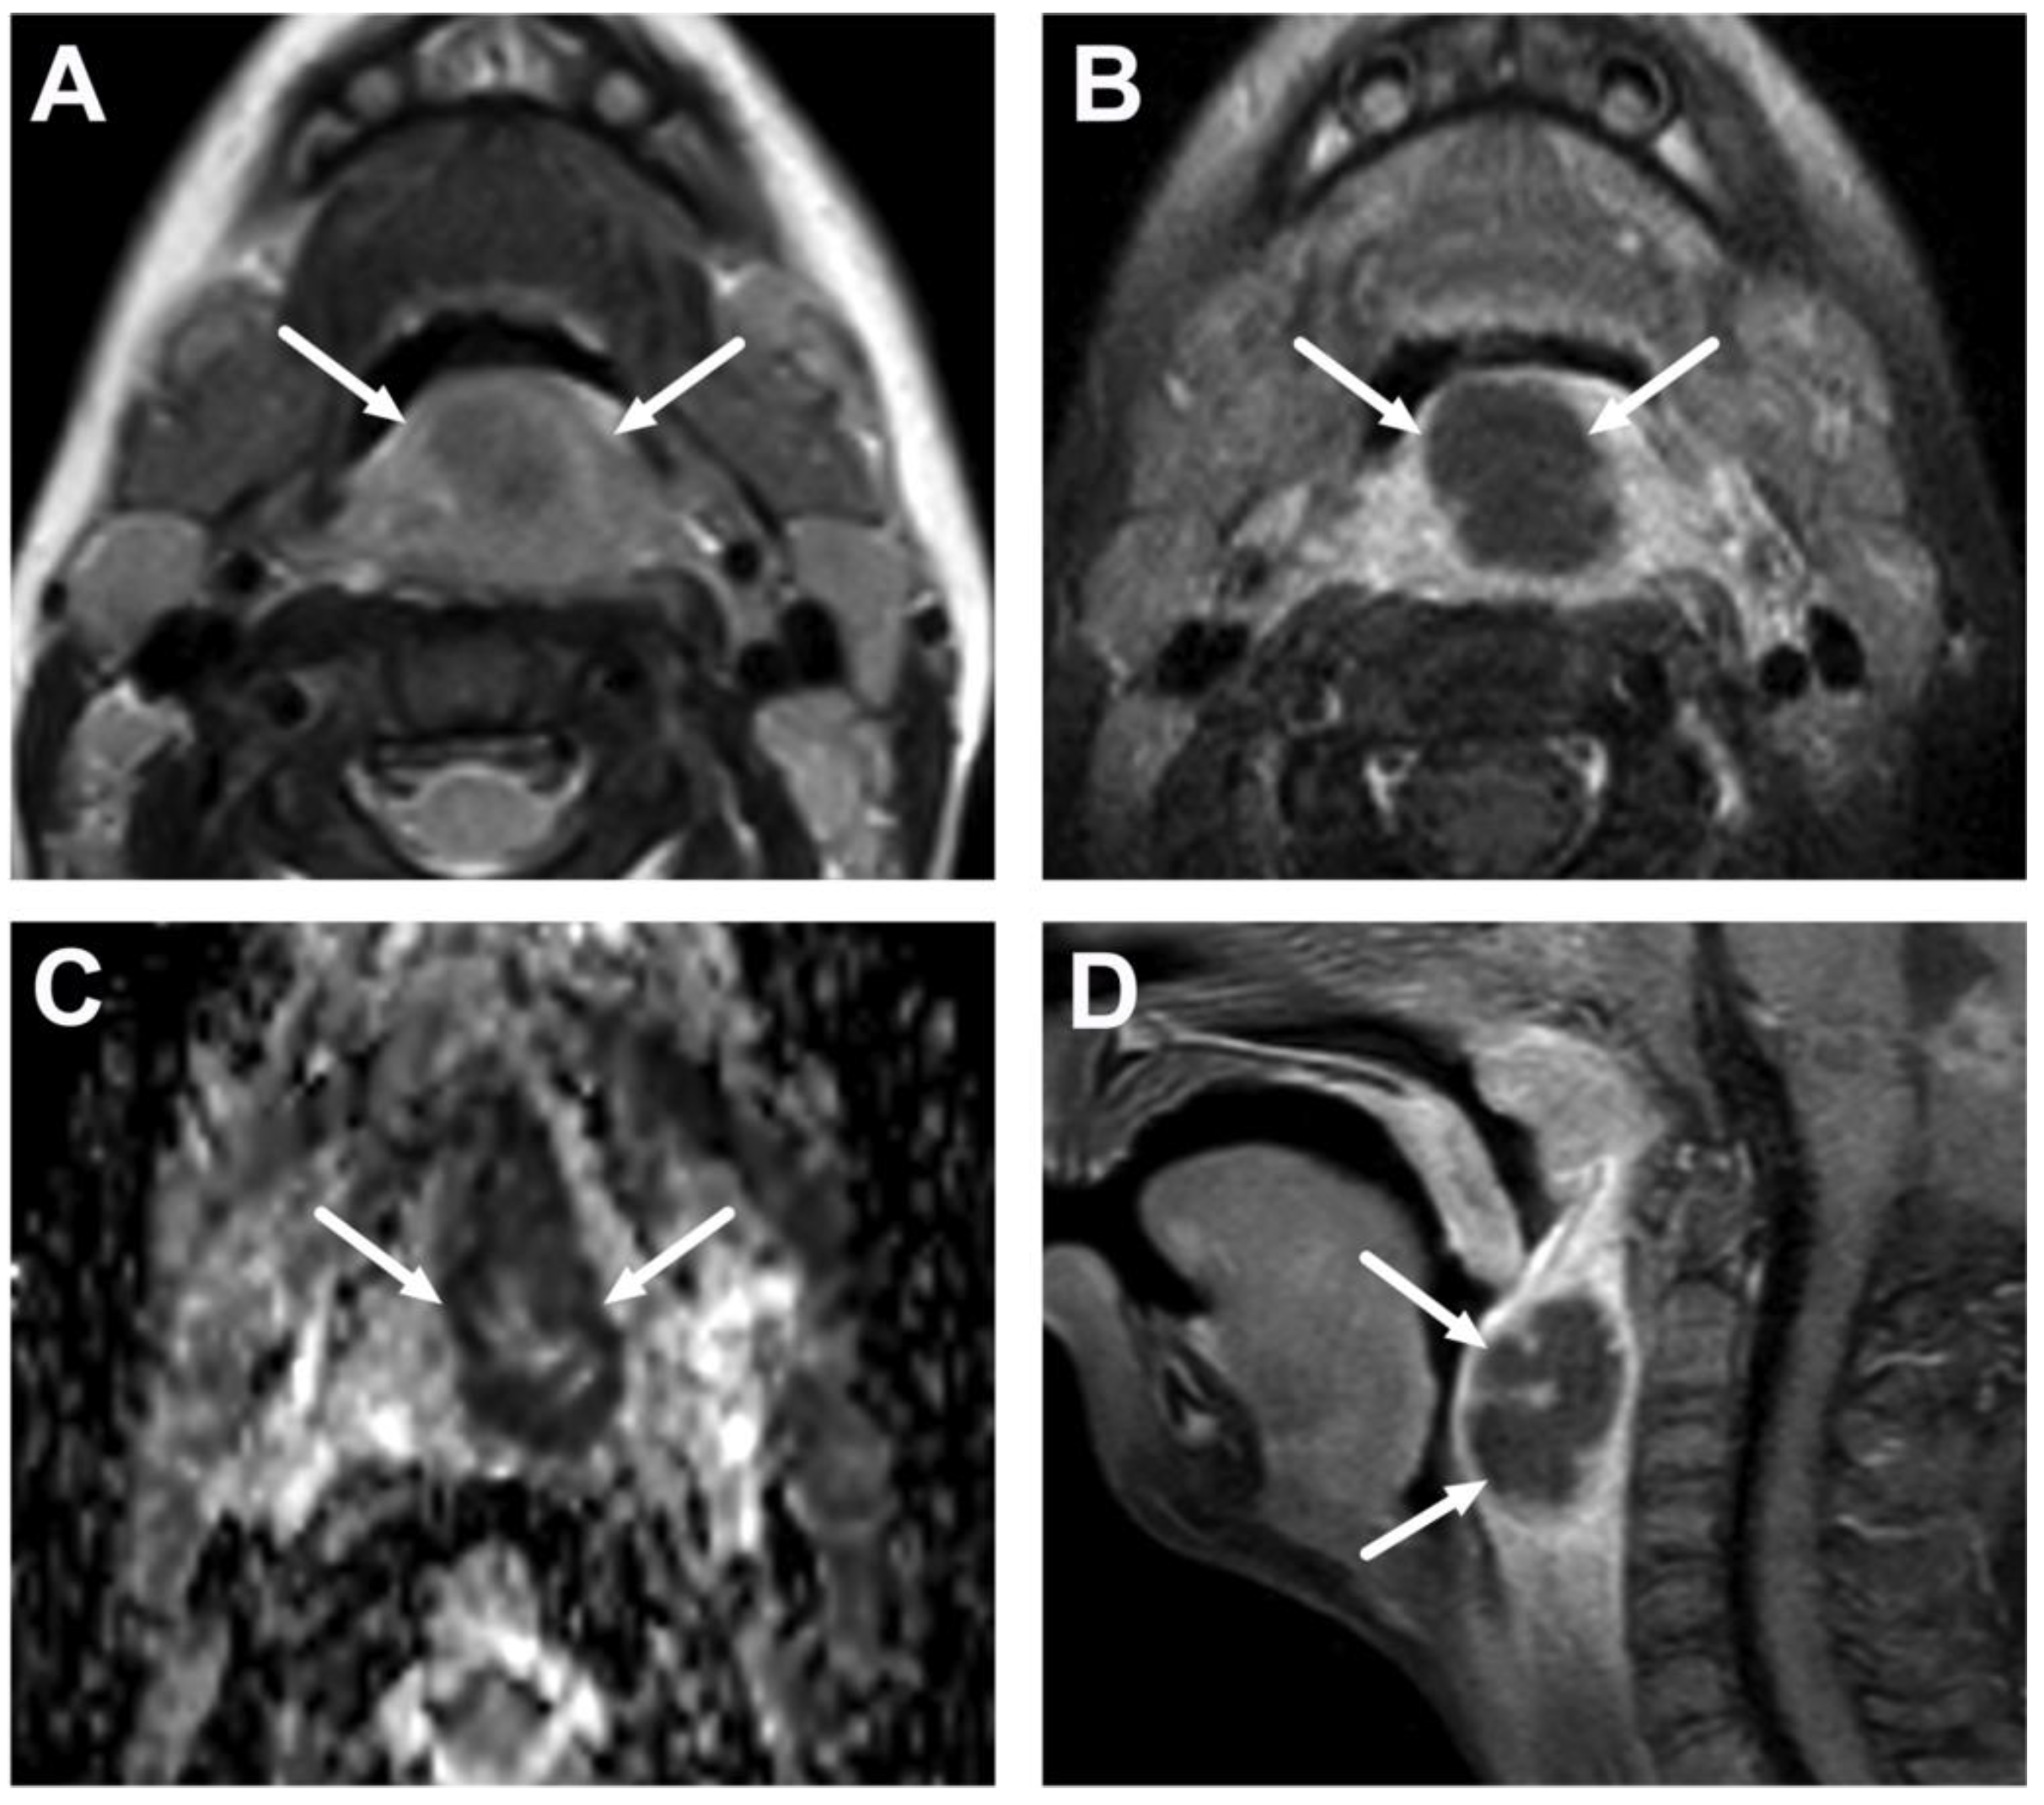

4.1. Tonsillitis, Peritonsillar Abscesses, and Parapharyngeal Abscesses

| Abscess | T1 SE T2 Dixon (water) DWI post-contrast T1 Dixon (water) | Non-enhancing collection with low ADC values enclosed in abnormally enhancing soft tissue edema. | Detection of an abscess usually requires operative consideration and exact abscess location, and extensions are useful in operative planning. | Abscesses may have an intermediate T2 signal content; blood products and/or postoperative status may complicate abscess assessment; necrotic lymph nodes may be misinterpreted as suppurative lymphadenitis. |